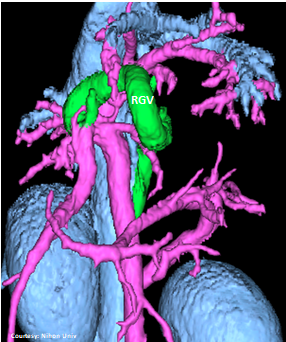

“LGC +PancV -GSV” Left Gastro-Caval Shunt with Pancreatic Vein contribution and absent Gastro-splenic vein (GSV does not enter PV)

Courtesy: Nihon Univ

WEISSE 2022